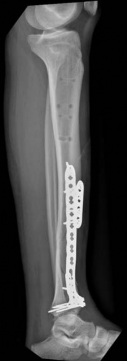

With the articular surface reconstituted, the surgeon's focus shifts to bridging the complex metaphyseal-diaphyseal dissociation. A pre-contoured anatomical locking plate is slid submuscularly or subcutaneously along the diaphysis using a MIPPO technique. The plate is positioned on the anterolateral or medial surface, depending on the preoperative plan and soft tissue constraints.

Image

The distal portion of the plate is secured to the reconstructed articular block. It is imperative that the distal locking screws are placed parallel to the joint space, forming a rigid subchondral raft that supports the articular cartilage. Fluoroscopy is utilized extensively to ensure no screws have penetrated the joint. Once the distal block is secured to the plate, the diaphyseal segment is aligned. Length, alignment, and rotation are restored using manual traction or the femoral distractor. The proximal portion of the plate is then secured to the diaphysis using a combination of non-locking screws (to pull the bone to the plate) and locking screws (to create a fixed-angle construct). The working length of the plate is maximized by leaving several screw holes empty over the zone of comminution, promoting secondary bone healing.